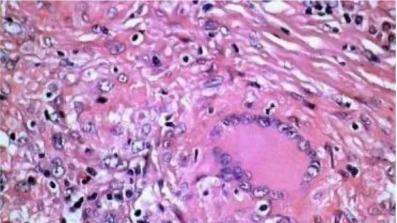

2.天狼猩红染色法

用途及原理:胶原与酸性染料反应强烈。天狼星红作为强酸性染料,与胶原纤维反应产生双折光现象。染色后胶原纤维显红色,胞核显绿色,其余显黄色。偏光显微镜可分辨4种胶原纤维类型。